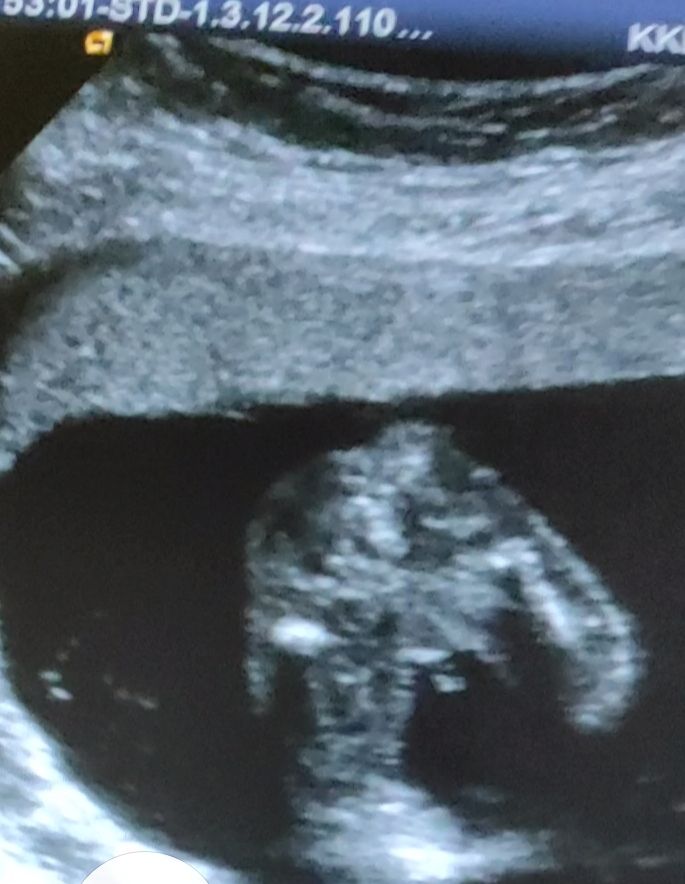

Изображение Паренёк у нас Елизавета,

09.10.2023